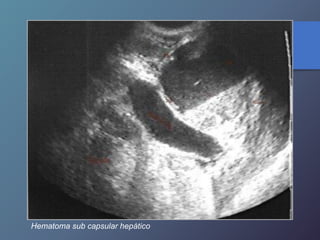

Traumatismo Hepático

• La lesión hepática es a predominio del lóbulo derecho.

• Mayor particularidad en segmento posterior.

• Mayor frecuencia por laceración peri vascular.

• Se producen hematomas subcapsulares,

pericapsulares o aislados.

• La hemorragia en las primeras 24 horas es ecogénica y

posteriormente se hace mas hipoecogénica.

• Entre las dos o tres semanas se puede observar gran

cantidad tejido de granulación.

Hígado post- trauma

Hematoma sub capsular hepático

Traumatismo Hepático • Lalesión hepática es a predominio del lóbulo derecho. • Mayor particularidad en segmento posterior. • Mayor frecuencia por laceración peri vascular. • Se producen hematomas subcapsulares, pericapsulares o aislados. • La hemorragia en las primeras 24 horas es ecogénica y posteriormente se hace mas hipoecogénica. • Entre las dos o tres semanas se puede observar gran cantidad tejido de granulación.